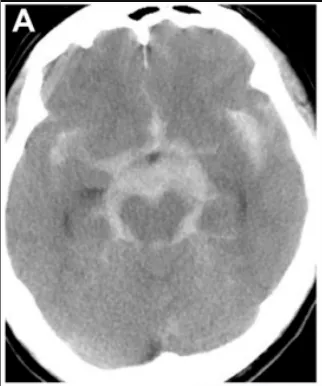

尽管大多数颅内血管畸形被认为是在先天基础上形成的,但它们在产前极少被发现,在新生儿和婴儿中也并不常见。这一特定患者群体的临床表现,最常见的特点是由大体积颅内出血引起的颅内...